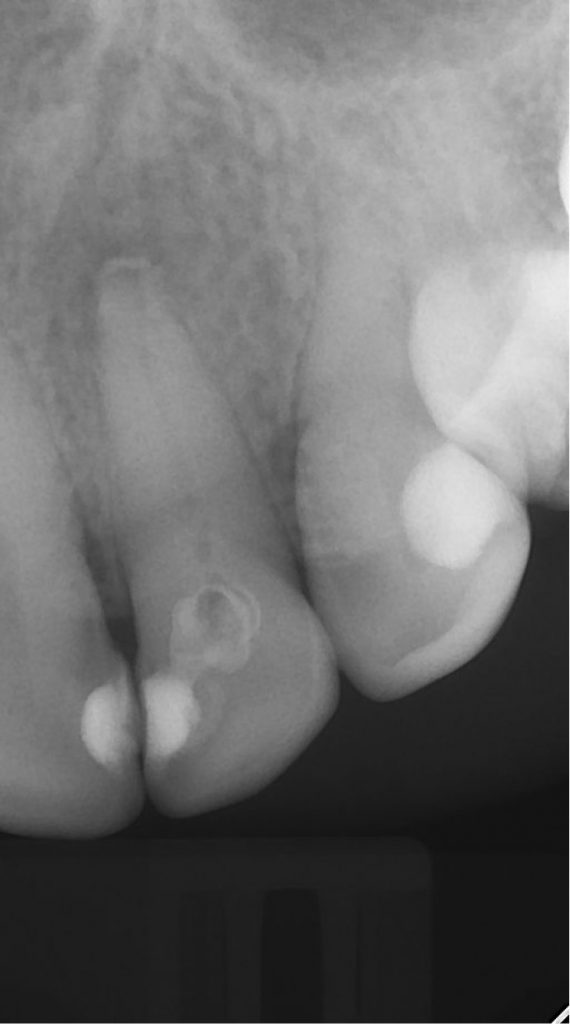

Streszczenie: W pracy przedstawiono dwa przypadki kliniczne przewlekłych zapaleń tkanek okołowierzchołkowych o charakterze ziarniniaków. Po zastosowaniu dokanałowo opatrunków czasowych w postaci preparatów wodorotlenkowo-wapniowych, które wykazują działanie przeciwbakteryjne, osteo- i odontotropowe, doszło do wygojenia struktur przyzębia okołowierzchołkowego. Warunkiem powodzenia tego dwuseansowego leczenia było szczelne zamknięcie ubytku między wizytami, które zapobiegło reinfekcji systemu kanałowego.

Summary: The paper presents two clinical cases of chronic periapical granuloma inflammation. After the use of temporary fillings in the form of calcium hydroxide material, which has antibacterial, osteotropic and odontotropic effects, the periapical periodontal structure was healed. The condition to ensure the success of this two-session treatment was the tight closure of the cavity between visits, which prevented the re-infection of the root canal system.